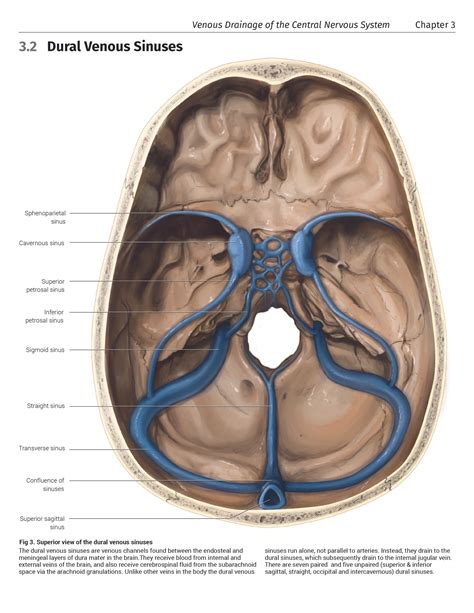

The Inferior Sagittal Sinus is a critical component of the venous drainage system in the brain, playing a pivotal role in maintaining cerebral health. This sinus is a venous channel that runs along the inferior border of the falx cerebri, a fold of dura mater that separates the two cerebral hemispheres. Understanding the anatomy, function, and clinical significance of the Inferior Sagittal Sinus is essential for medical professionals, particularly those involved in neurosurgery and neurology.

Anatomy of the Inferior Sagittal Sinus

The Inferior Sagittal Sinus is a small, midline venous structure that collects blood from the medial surfaces of the cerebral hemispheres. It begins at the crista galli, a bony projection at the front of the cranial cavity, and runs posteriorly along the inferior border of the falx cerebri. The sinus terminates by draining into the straight sinus, which is formed by the confluence of the Inferior Sagittal Sinus and the great cerebral vein of Galen.

The Inferior Sagittal Sinus receives blood from several tributaries, including:

• Medial striate veins

• Anterior cerebral veins

• Superior cerebral veins

These tributaries drain blood from the medial aspects of the frontal, parietal, and occipital lobes, ensuring efficient venous return from these regions.

Function of the Inferior Sagittal Sinus

The primary function of the Inferior Sagittal Sinus is to facilitate the drainage of deoxygenated blood from the brain. This venous drainage is crucial for maintaining cerebral homeostasis and preventing the accumulation of metabolic waste products. The sinus acts as a conduit, channeling blood from the medial surfaces of the cerebral hemispheres into the straight sinus and ultimately into the venous sinuses of the dura mater.